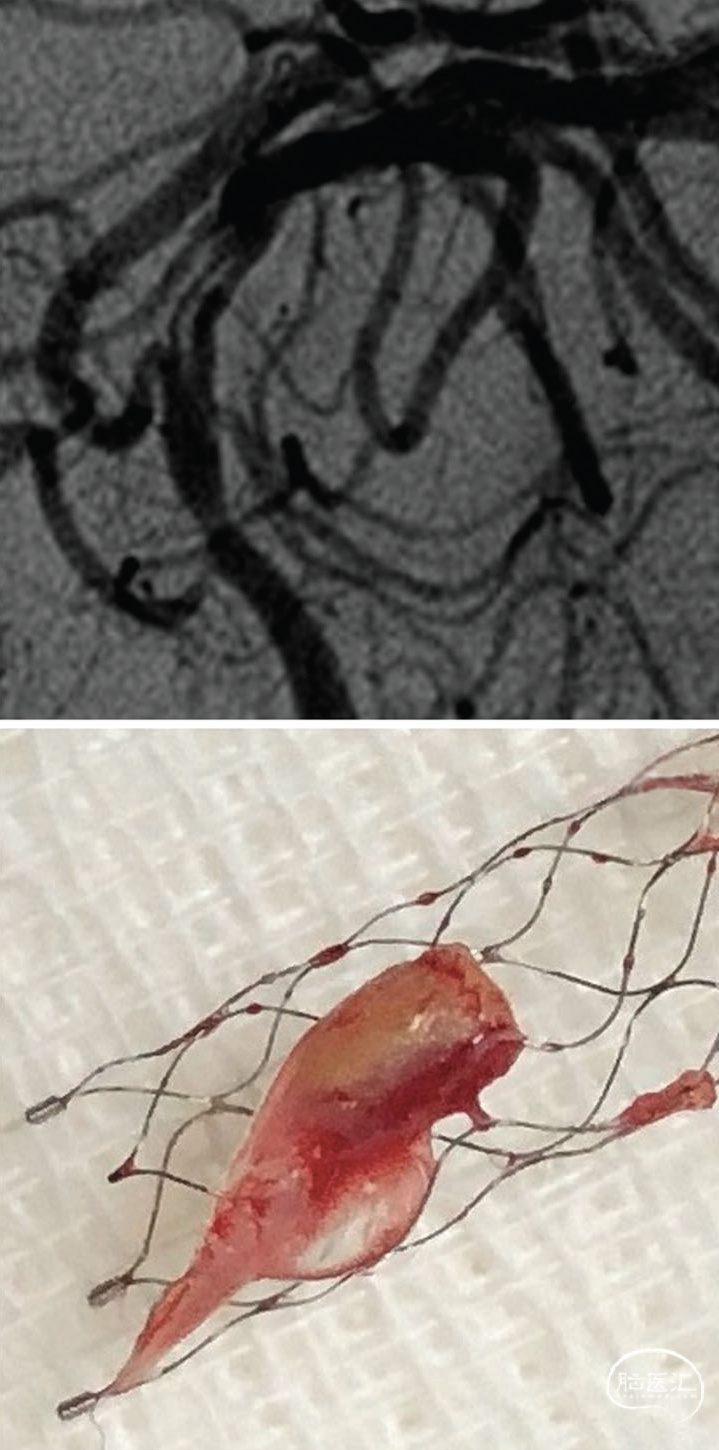

图1. 血管造影中的充盈缺损及其诱因软组织形态学表现。A. 右侧大脑中动脉可见充盈缺损(箭头所示)。B. 在右侧大脑中动脉区域释放取栓支架后,取出的软组织标本(尺寸为1.0×0.2×0.1厘米):

一名65岁男性,患有未控制的高血压、冠状动脉疾病及重度吸烟史,因嗜睡及左侧偏瘫2小时至急诊就诊。入院时美国国立卫生研究院卒中量表(NIHSS)评分为15分。头部计算机断层扫描(CT)未显示出血,阿尔伯塔卒中项目早期CT评分(ASPECT)为10分。立即按0.9 mg/kg剂量静脉注射重组组织纤溶酶原激活剂(rt-PA)进行溶栓治疗。同期CT血管造影显示右侧颈内动脉严重狭窄及大脑中动脉闭塞,后续数字减影血管造影(DSA)在介入治疗前确认上述病变(视频A、B)。完成右侧颈动脉支架置入术(视频C、D)后,对右侧大脑中动脉行机械取栓,取出大块暗红色血栓实现血管再通。但DSA发现大脑中动脉内存在活动性充盈缺损,从豆纹动脉分支处移行至远端大脑中动脉(图1A;视频E),导致延迟灌注(视频F)。再次置入取栓支架后,取出灰色软组织(图1B),右侧大脑中动脉实现无充盈缺损的再通(视频G)。

术后患者意识完全清醒,NIHSS评分降至6分。病理分析显示:首次抽取的暗红色血栓为混合性血栓,而后续导致充盈缺损的灰色软组织包含动脉壁成分,经平滑肌肌动蛋白免疫组化染色及弹力纤维染色确认(图2A、B)。住院10天后出院时神经系统检查正常,改良Rankin量表和NIHSS评分均为0分。